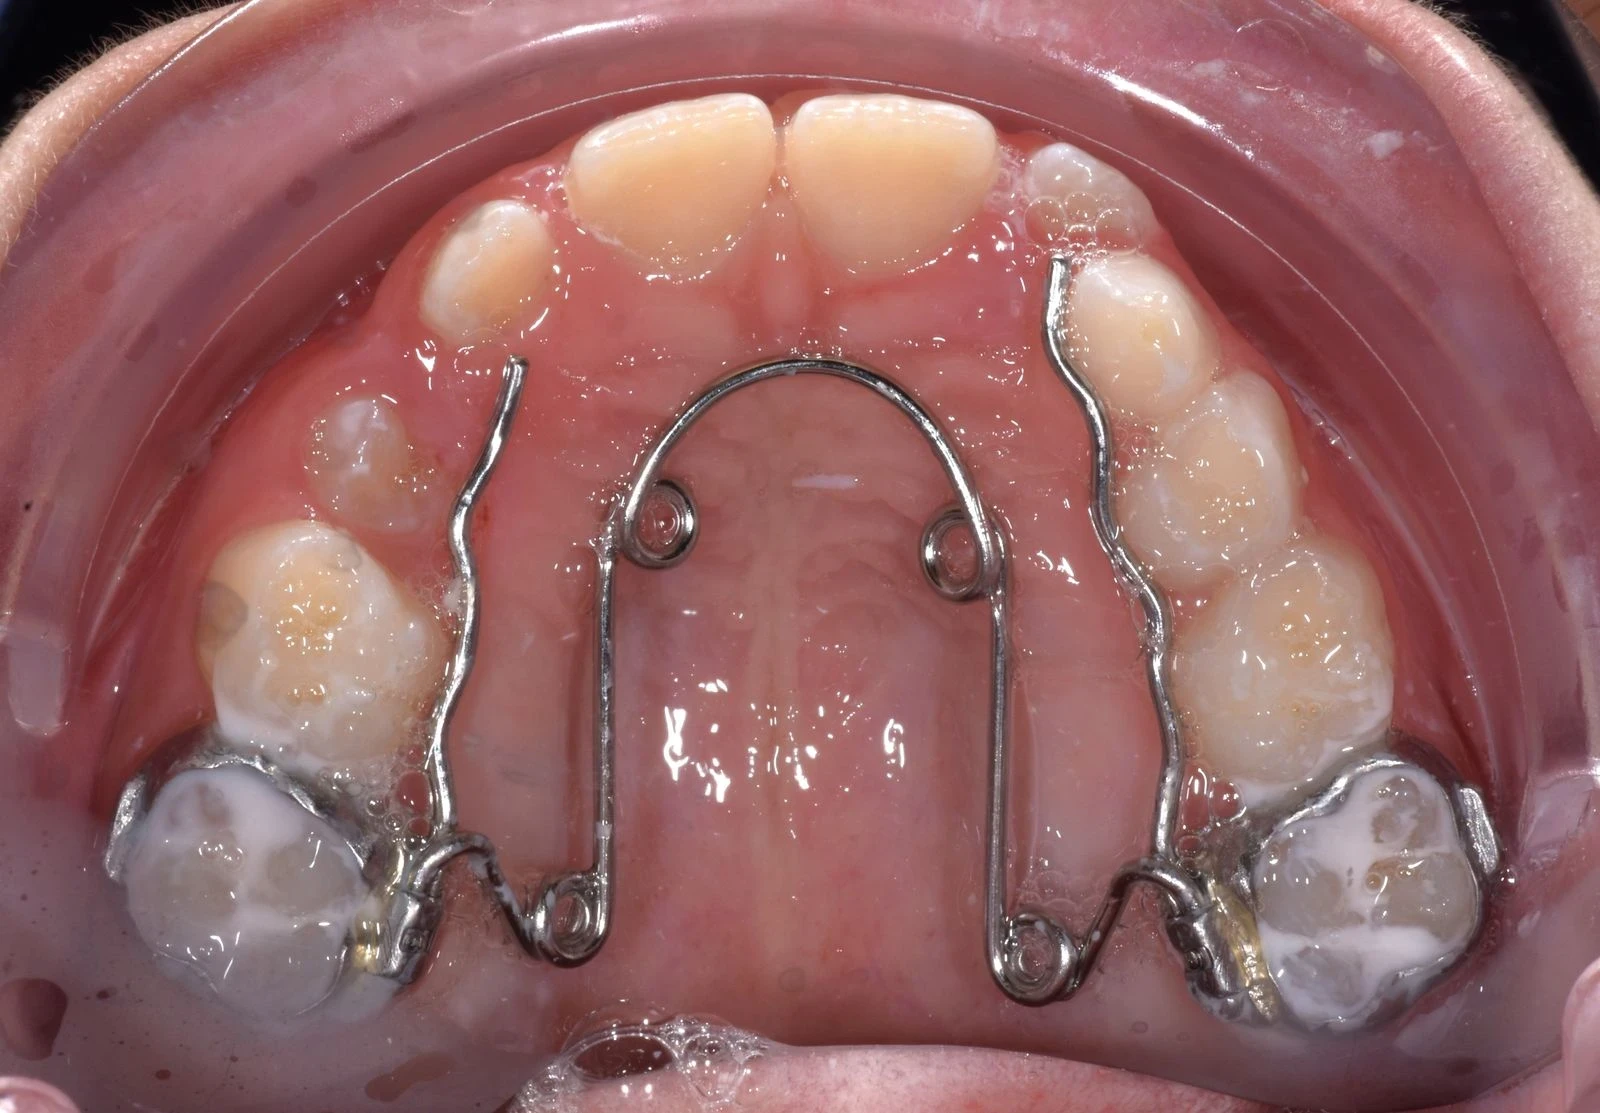

Contentions

Qu'est-ce que la contention dentaire et à quoi sert-elle ?

La période de contention dentaire est tout aussi importante que la période active du traitement d’orthodontie.

À la fin d'un traitement, il est nécessaire de consolider les résultats obtenus afin d’éviter que les dents ne se déplacent à nouveau. En effet, après le port d'un appareil dentaire, qu'il s'agisse de bagues classiques, d'un appareil lingual ou même d'aligneurs transparents, le risque de récidive est important, en raison de multiples facteurs tels que :

Il s'agit donc d'une période incontournable, qui va permettre de maintenir le bon alignement des dents, obtenu à l’issue du traitement orthodontique actif.

On distingue deux types d'appareils de contention :

Les contentions fixées : il s’agit de fils de contentions que l’on colle sur les faces internes des dents.

Les contentions amovibles : il s’agit de gouttières de contention, similaires aux gouttières d’alignement, mais dont la rigidité est différente et qui ne se portent que la nuit.